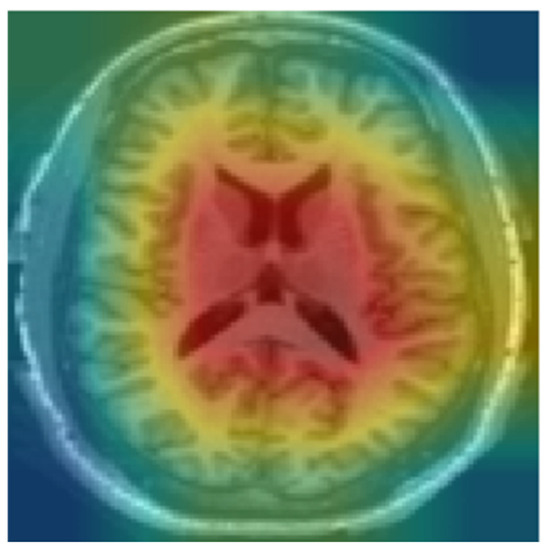

We used Grad-CAM to identify critical regions that influenced the model’s classification. Since the model was trained on the middle slices, Grad-CAM prominently displayed the lateral ventricles as shown in Figure 8. Ventricular enlargement is among the most prominent signs of AD. The regions identified by Grad-CAM are in line with the current medical understanding of AD, reducing interpretation complexity, increasing transparency in the interpretation of model decisions, and enhancing confidence in the model.

Figure 8. Heat map using Grad-CAM for CN.